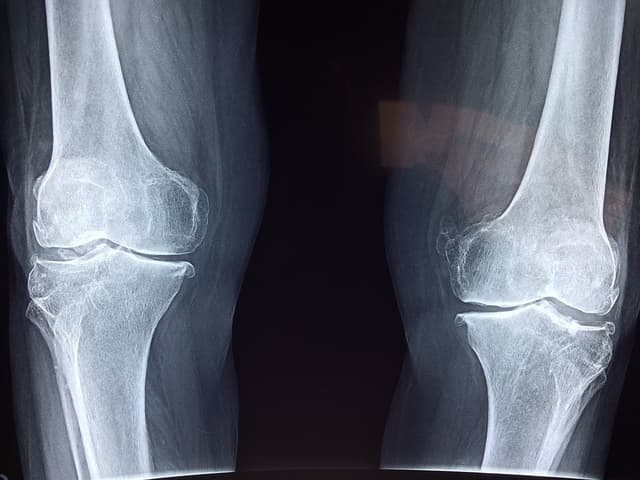

Paget’s disease is a chronic bone disease of the skeleton. In a healthy bone, a process known as remodeling begins to remove old parts of bone and replace them with fresh bone. Paget’s disease causes the new, fresh bone to grow abnormally in shape and be weak and brittle. It is a disease that more often affects older individuals and can occur in the legs, spine, pelvis and skull.

Individuals with Paget’s disease of the bone often may have no noticeable symptoms. However, if they do experience symptoms, it is often bone pain. As this disease causes the body to create new bone at an accelerated rate, the remodeling generates weaker, softer bone, which can lead to bone pain, fractures and deformities. The disease may only affect one or two areas of the body or it can become widespread. Common signs and symptoms are often based on which area of the body the disease is affecting. This includes:

Leg: When bones become weak, they can start to bend, which can cause the individual to become bow-legged. Misshapen or enlarged bones in the legs can create added stress in nearby joints, which can lead to osteoarthritis in the hip or knee.